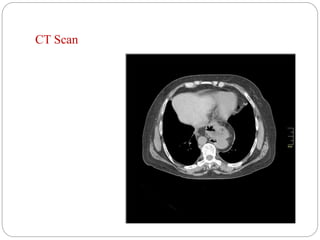

 CT Scan

Useful especially for evaluation of a paraesophageal hernias to

identify the size of the hernia and other organs which may be

involved.

CT Scan